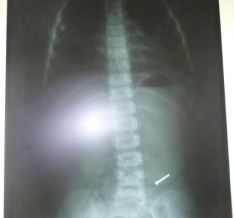

El médico del área de Neonatología de dicho nosocomio, Carlos Aréstegui Ramos, dispuso sacarle una placa radiográfica y corroboró las sospechas, encontrando un clavo alojado dentro de sus intestinos lo cual fue una sorpresa para sus colegas que estuvieron presentes durante la revisión de la radiografía.